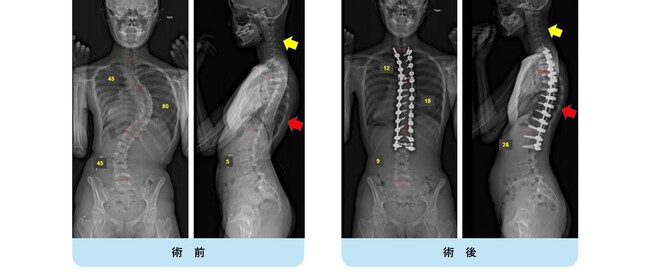

思春期特発性側弯症の全脊椎レントゲンで背骨がSの字に曲がっています。最も曲がっている箇所は52°で、成長終了後も高率にカーブが進行し続けます。50°前後の側弯であれば手術により80%以上まっすぐにすることができます。通常は70%程度の矯正率で良いとされていますが、本来出来るだけまっすぐする手術であり、バランスが損なわれるようなことがなければ我々は矯正率80%を目指しています。

この症例は術後の側弯角は8°で、矯正率は85%でした。また肩バランスも水平で保たれています。また注目すべきは腰の曲がりです。術前のレントゲンをみると腰にも側弯があるのが分かります。(黄色矢印)

腰椎の可動性を残すために、胸椎の側弯に絞って矯正固定を行い腰椎の側弯が引っ張られて改善することを期待しました。術後のレントゲンをみると金属が埋め込まれていない腰椎の側弯が大きく改善しているのが分かります。(黄色矢印)

この症例についても、横から見ると術前に右の背中が肋骨隆起(リブハンプ)により出っ張っています。(赤色矢印)

手術により側弯だけでなく回旋矯正、生理的胸椎後弯形成が成され、術後は右の背中の出っ張りがなくなり生理的な背中全体の丸みが復元されているのが分かります。(赤色矢印)

このように我々は側弯だけでなく、本来の生理的なshapeを取り戻すことを目標に治療を行っています。